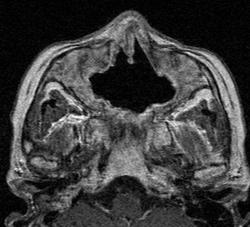

Кисты.